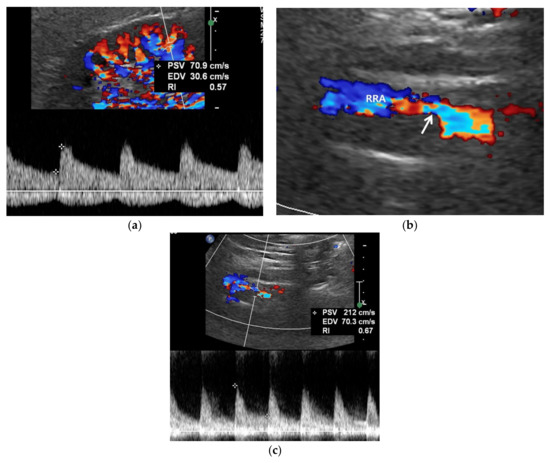

Figure 4.

A high reno-aortic PSV ratio in a 78-year-old man. (a) Spectral Doppler US shows that a PSV is measured 83 cm/s 1–2 cm below the origin of superior mesenteric artery. (b) Spectral Doppler US shows that a PSV is measured 318 cm/s in the poststenotic area, showing turbulence flow. The frequency shift in the proximal left renal artery (arrow) is not sufficient to precisely quantify. The high-PSV RAR is more than 3.8 (318/83) because the PSV in the RAS should be higher than that in the poststenotic area.

Spectral Doppler US quantitatively measures the velocity of blood flow in the stenotic renal artery (Table 4). The peak systolic velocity (PSV) within the stenotic renal artery is frequently more than 180–200 cm/s [4,22,23,24,25,48] (Figure 2 and Figure 3). If PSV is more than 180 cm/s, the sensitivity and specificity for RAS range from 85–97% and 72–98%, respectively [24,25,28,31]. In case of unilateral RAS, PSV is significantly different between the two renal arteries. At this point, two simple concepts should be kept in mind: first, the normal PSV values in normal renal arteries without stenosis (about 70–100 cm/s), and, second, angle correction is essential to obtain reproducible and accurate measurements of PSVs. If the PSV of the renal artery is ≥3.5-fold that of the aorta (renal-to-aorta ratio (RAR)), it can suggest RAS [26,27,29,49] (Figure 4). The PSV RAR is another good indicator for identifying RAS. If RAR is 3.5 or greater, the sensitivity and specificity ranges are 91–92% and 71–95%, respectively [26,27,29]. It is important to determine where PSV is measured within the aorta because it differs by region-of-interest location. First, radiologists or sonographers should find the origin of the superior mesenteric artery (SMA) during the sagittal US scan; then, the PSV region of interest should be 1–2 cm below the SMA because the renal arteries are located below the origin of the SMA.